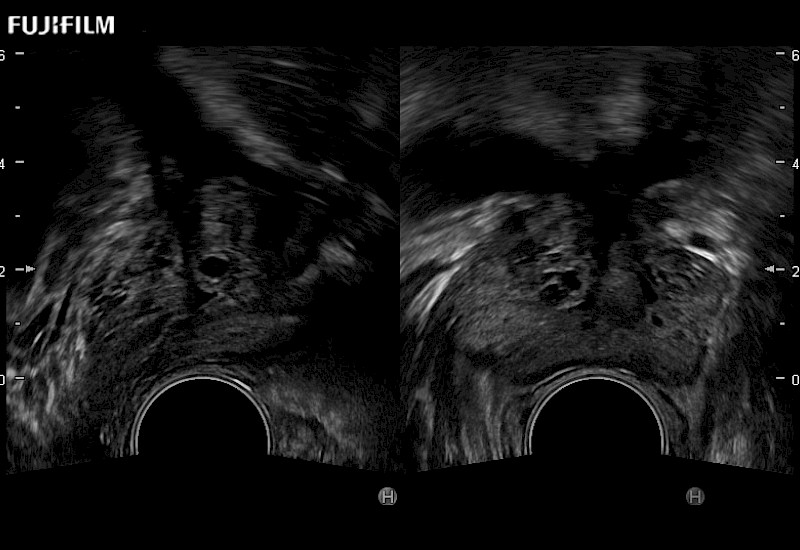

Ideal transducer for Transperineal Biopsy, Hydrogel Spacer Placement, Brachy LDR & HDR, Cryo, and MPMRI procedures.

Main Specifications: